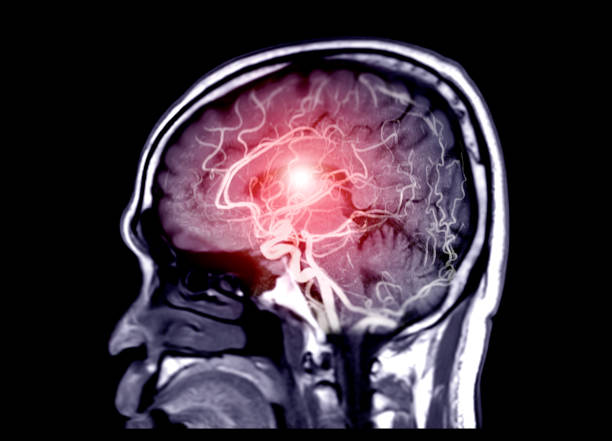

뇌졸중

뇌동맥류가 크거나 위치가 민감한 경우 뇌졸중을 초래할 수 있습니다. 뇌졸중은 뇌의 혈관에 혈전이 생기거나 출혈이 발생하여 뇌의 기능이 일시적으로 또는 영구적으로 손상되는 상태를 말합니다. 이러한 증상은 뇌동맥류의 위치와 크기에 따라 발생할 수 있으며, 응급 상황이므로 즉각적인 치료가 필요합니다.